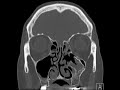

Odontogenic Ossifying Fibroma

These images demonstrate a mass arising from the left maxillary alveolar ridge with areas of ground glass opacity, cementum-like density abutting the roots of the left third maxillary molar, and expansile extension into the left maxillary sinus. The left maxillary antrum is widely patent. This appearance is most consistent with a benign odontogenic ossifying fibroma which can be followed radiographically if asymptomatic. There is mild sinus inflammatory changes of the remaining paranasal sinuses.